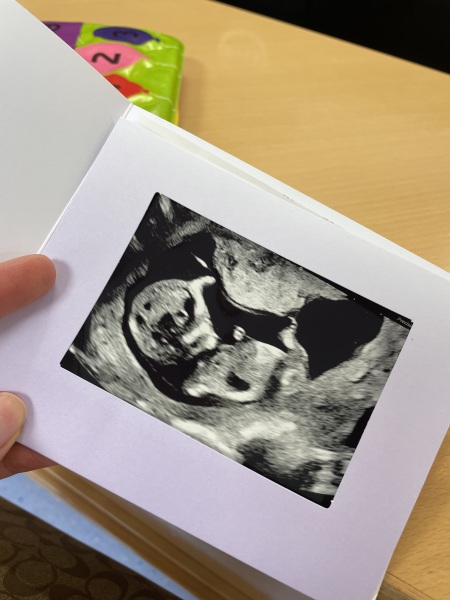

I realise the nub theory isn't 100%, however I've posted my scan on multiple nub sites and been told each time it's a very clear nub and they're 99%! Il post it here too so you can all have a guess 😉.

Just curious really if anyone also has a "clear nub" for it to then be wrong. Im happy either way FYI. The bun was never visible on the scans with my first.

Hi, I am another mum that's had to jump on the nub theory bandwagon. Early Glimpse and Nub Techs have both said boy but The Nub Whisperer has said girl. I will share all images, the last image is of my current pregnancy on top and my son on the bottom just for comparison. I was measuring 12 weeks and 5 days at scan. I have a gender scan in 19 days!!! We can't wait 🥰 please let me know about your experiences with nub theory and what you think of my baby scan ❤️